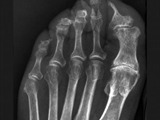

El joven admitió que unas semanas antes había tenido una pelea con otro hombre, y en medio de la riña, una patada suya impactó en la mandíbula de su adversario, lo que le provocó una fractura en la mandíbula y el desprendimiento de un par de dientes. Uno de ellos, debido a la fuerza de la patada, quedó incrustado en su pie. La herida cerró y la pieza dental quedó dentro de su cuerpo. Inmediatamente los doctores ordenaron una intervención quirúrgica para removérselo.

La operación fue un éxito, pero el muchacho todavía sigue en observación, ya que como los dientes están en contacto con la saliva, líquido que puede alojar unas 200 especies de micro organismos, puede haber una alta chance de contraer infecciones.